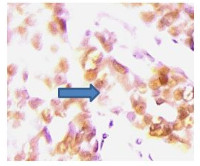

The immunological and virological correlates of Cervical Precancerous Lesions among HIV-Infected Women on ART in Faith Alive Hospital, Jos, Nigeria

John Onyeji, Olabanjo Okunlola Ogunsola, Emmanuel Osayi, Oluseye Ayodele Ajayi, Mercy Wakili Isichei, Christian Ogoegbunem Isichei, Perpetua Chidiebere Christopher

Abstract 73 | PDF Downloads 44 EPUB Downloads 41

Page 873-883